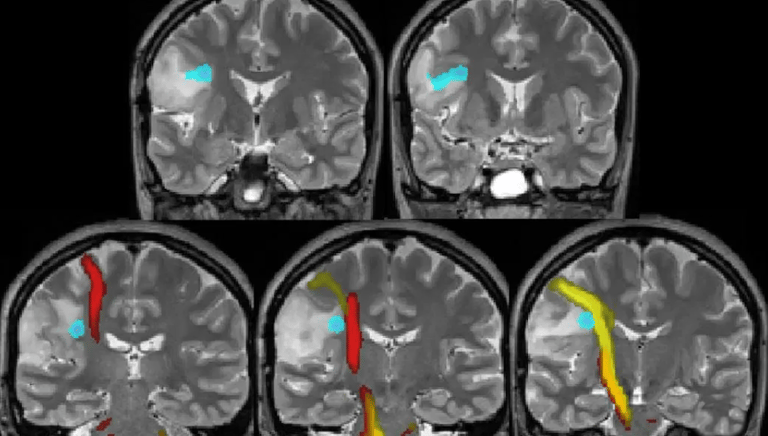

Published in the journal Nature by psychiatrists at Weill Cornell University. Functional magnetic resonance imaging (fMRI) scanners were used to compare the brain activities of clinically depressed and healthy people.